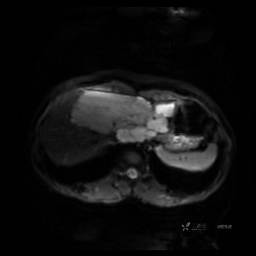

MR平扫+增强

每个序列一张图像(图像太多了,恕不一一发上来)